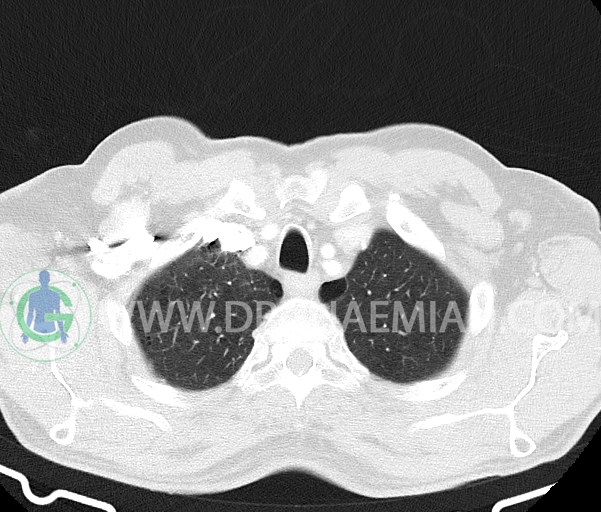

در سی تی اسکن اسپیرال ریه و مدیاستن- شکم و لگن با و بدون کنتراست خوراکی و وریدی (مولتی دیدکتور 16 با مقاطع ظریف و بازسازی های ساژیتال و کرونال) :

تراشه و برونش های اصلی نرمال اند.

توده ریوی، پلورال افیوژن، جابجایی محتویات مدیاستن، کلسیفیکاسیون، کیست، فیبروز ریوی و Collection مشهود نیست.

-bridging osteophytes در قسمت قدامی مهره های توراسیک

مشهود است